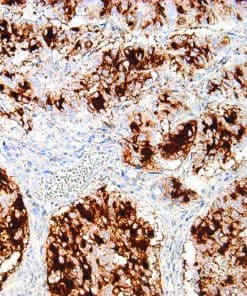

Thymidylate Synthase

Thymidylate Synthase (TS) is a crucial enzyme responsible for the synthesis of 2′-deoxythymidine-5′-monophosphate (dTMP) a precursor for thymidylate which is necessary for DNA replication and repair from 2′-deoxyuridine-5′-monophosphate (dUMP). In terms of cancer, TS is an important target for cancer treatment as the inhibition of TS and therefore nucleotide synthesis necessary for cell growth has shown to be a vital part for successful treatment against colorectal, pancreatic and breast cancers.

| Clone | IHC697 |

| Source | Mouse Monoclonal |

| Positive Control | Colon Cancer |

| Dilution Range | 1:100 – 1:400 |